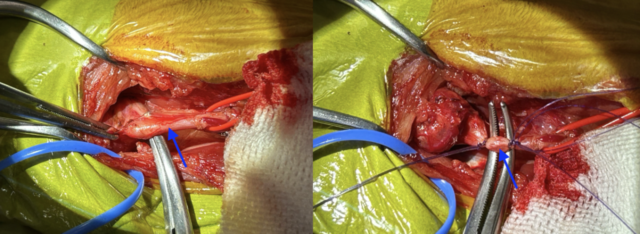

皮膚および皮下組織を切開し、筋肉の間を分けていくと腫瘍が確認できました(青丸)。

上述した通り、この腫瘍は頸の血管(青矢印)から発生するため、腫瘍を切除するためには血管を一緒に切除する必要があります、そのため、血管を糸で縛り切除しました。